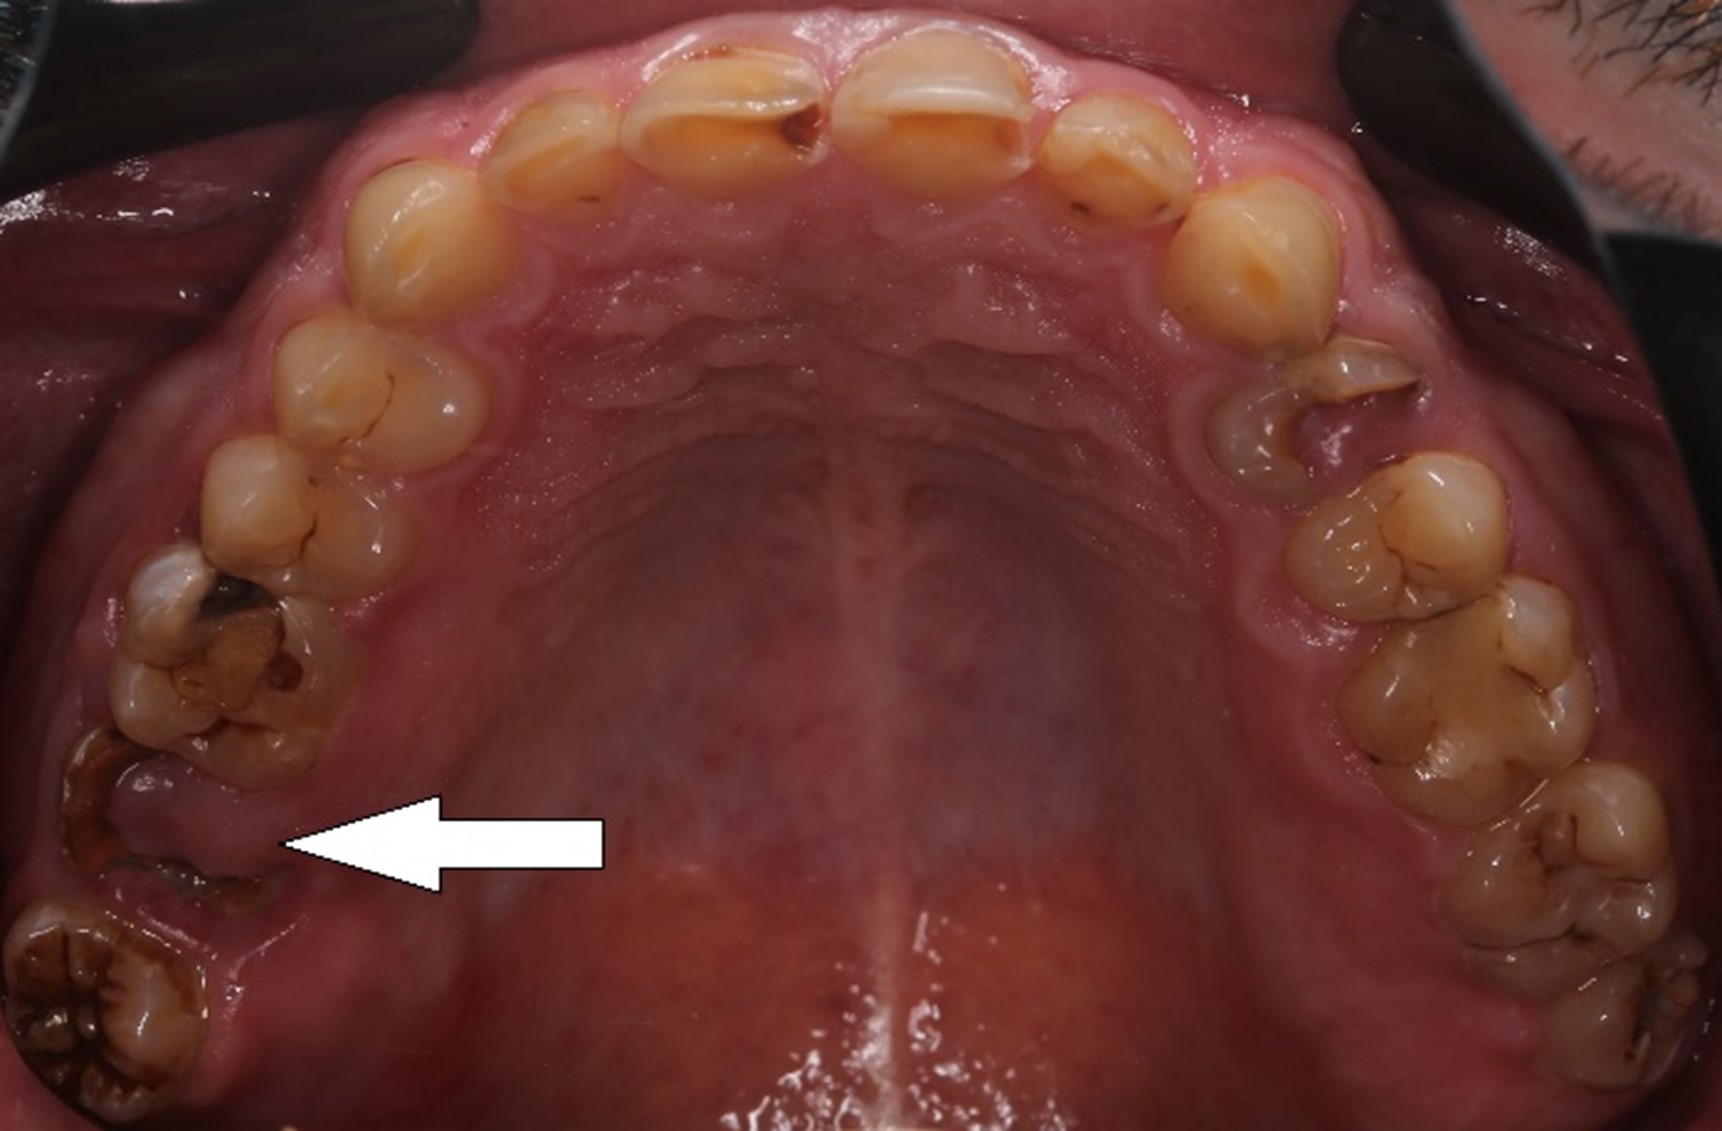

Напоминаю: он пришёл к нам вот в таком состоянии:

На нижней челюсти у него жевательных зубов не было вообще:

В жевательном отделе зубов практически нет. На зубах с первого по пятый появились небольшие фасетки стираний, которые означают, что прикус зафиксирован именно на них. Если они настолько отчётливые, как у Ивана, это значит, что зубы начинают стираться, и высота нижнего отдела лица уменьшается. Значит, придётся повышать прикус, чтобы вернуть височно-нижнечелюстной сустав и зубы в первоначальную здоровую позицию. Это будет моей задачей.

Смотрим дальше.

Такие разрушенные зубы, заросшие десной, кричат о необходимости имплантации

Кариозные процессы сигналят о терапевтической реабилитации и терапевтической санации полости рта

Воспалённые дёсны намекают на пародонтологию